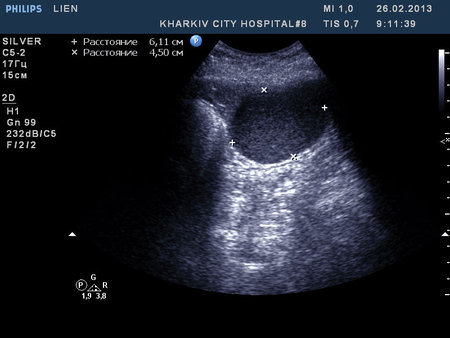

Re: образование селезенки

"Это становится интересным" © робот Вертер.

Рекомендовал КТ. Попробую узнать результат

Сегодня задренировал, содержимое - см. фото

Цитология: белковый преципитат, большое количество эритроцитов, лейкоцитов 5-8 в поле зрения.

Таким образом, видимо, в нашем случае это посттравматическая киста.